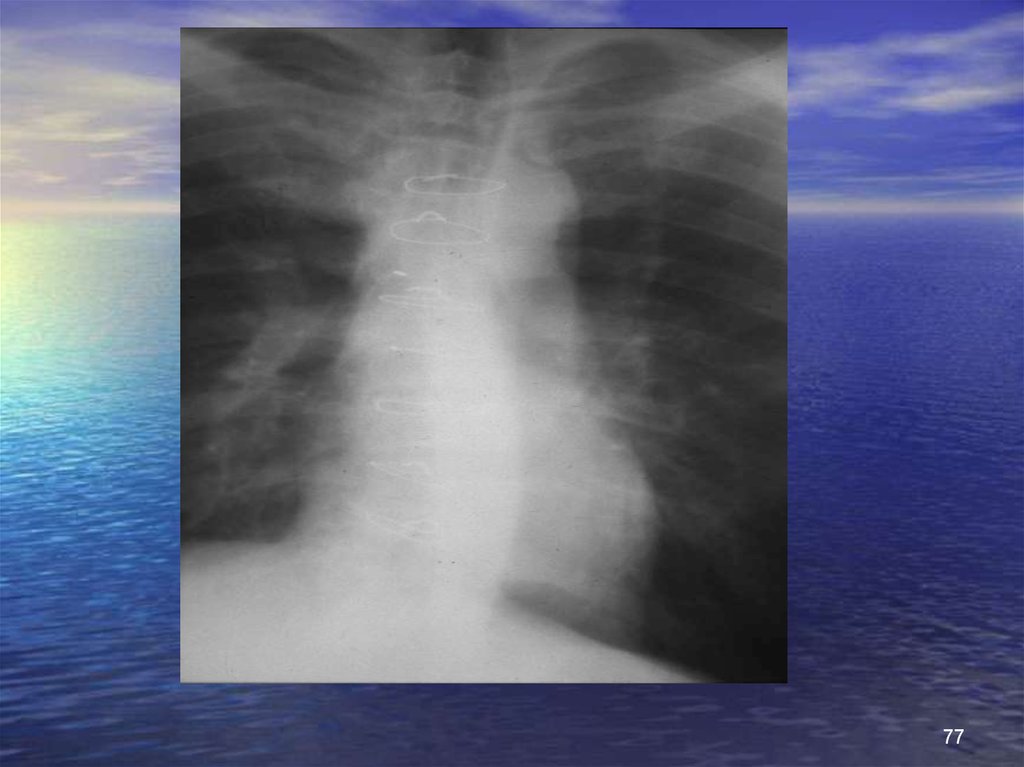

77.

77